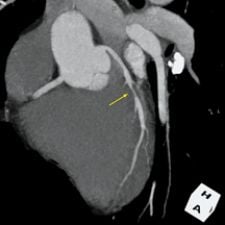

3-D volume rendering showing mid-LAD stenosis. Photo courtesy of TeraRecon Inc.